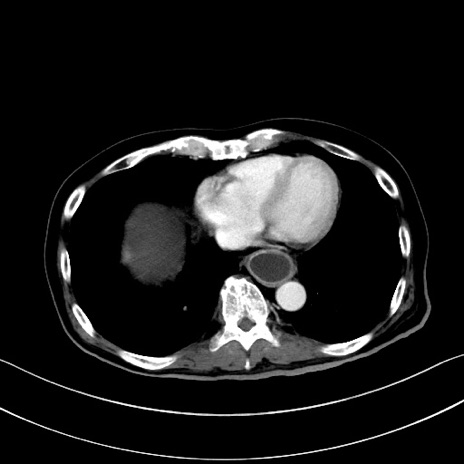

症例28(横断像)

【症例】60歳代男性

【現病歴】胃癌にて胃全摘後。食思不振が悪化し、夜中に嘔吐することがある。

【既往歴】胃癌、胃全摘、脾摘、胆摘後